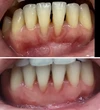

نزيف اللثة

أمراض الأسنان واللثة